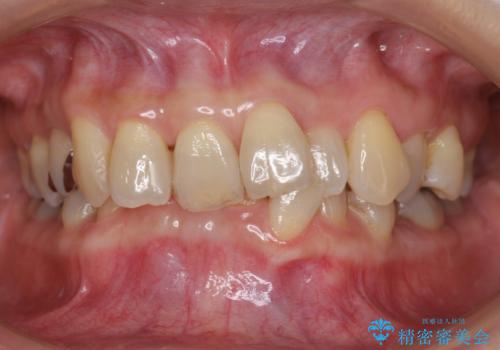

20代女性 受け口 手術をしなくても変わります

少し時間はかかりましたが、しっかり受け口を治すことができました。

口元も閉じやすくなりました。